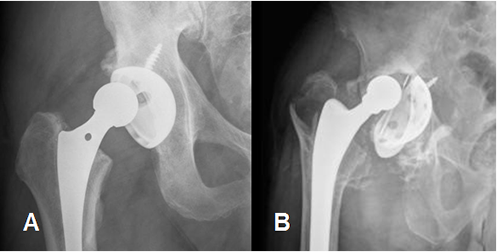

Fig 121. Luxación de la prótesis.

A: Rx AP. Subluxación de la prótesis.

B: Rx AP. Luxación de prótesis bipolar, con desplazamiento de los componentes acetabular y femoral.